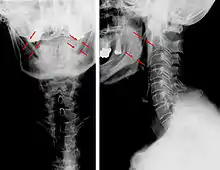

| Anteroposterior and lateral radiographs of cervical spine showing ossification of the stylohyoid ligament on both sides | |

Radiograph, lateral view showing joint-like formation in ossified stylohyoid ligament